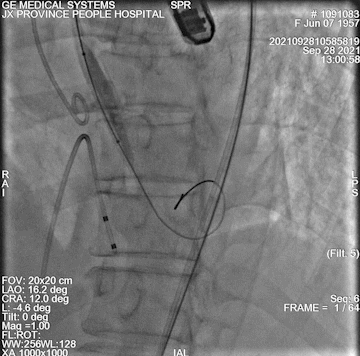

加硬导丝输送大鞘

球囊扩张

监护麻醉,右股动脉为主入路,左股为辅入路,通过瓣膜输送导丝直接起搏,选用18mm球囊扩张,使用VitaFlow Liberty™ 24瓣膜。